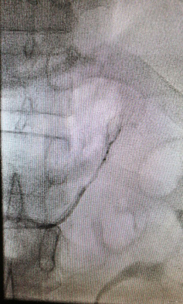

左側腎上腺靜脈插管